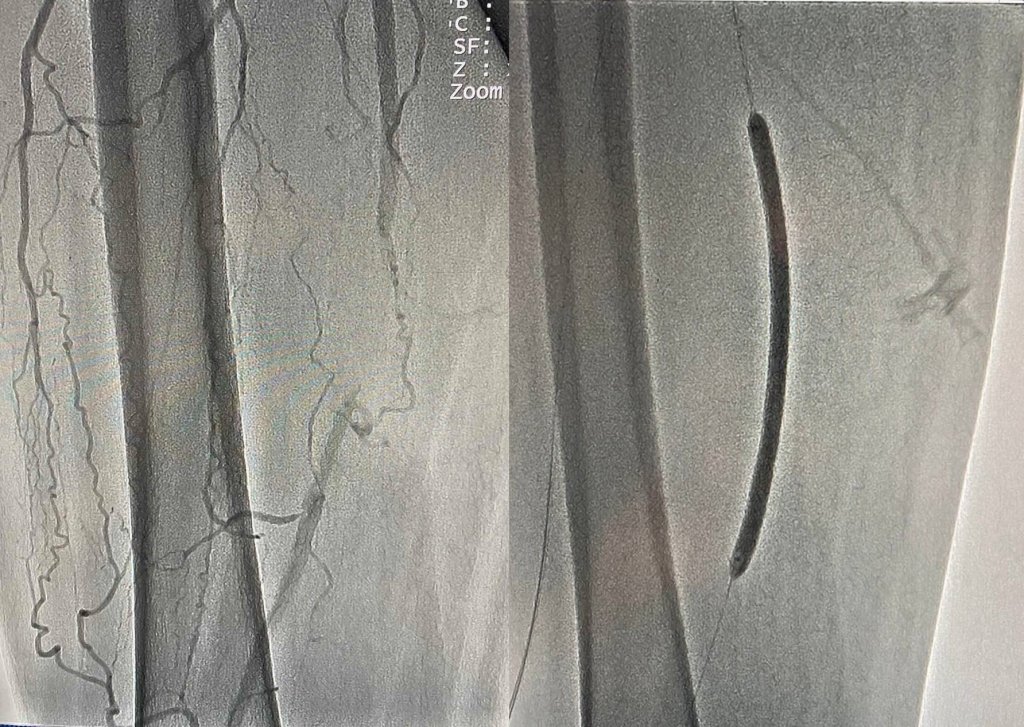

Врятувати ногу чоловіку можна було лише провівши стентування. Команда судинних хірургів на чолі з Олександром Голубом успішно виконала малоінвазивне оперативне втручання з відновлення кровопостачання

Стент був встановлений усього через один прокол. Це дозволило пацієнту вже наступного дня вільно ходити коридорами лікарні, а через три дні поїхати додому.